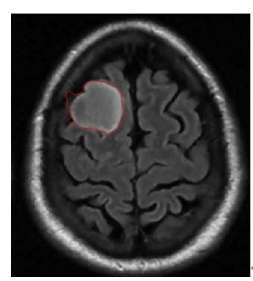

5.4 Results on brain MRI images

To achieve accurate segmentation of medical images, we have carefully tuned the parameters α, λ, and μ, which play a critical role in the performance of the DRLSE algorithm. These parameters control key aspects of the level set evolution, such as the smoothness of the contour (α), the fitting to the object boundaries (λ), and the regularization of the level set function (μ).

Using an empirical approach, we iteratively adjusted these values to obtain the best segmentation results for the images shown in Figure 10. Specifically, for brain MRIs, we found that setting α=0.5, λ=6, and μ=0.02 provided optimal segmentation results. These values effectively balance the trade-off between contour smoothness and accuracy in detecting object boundaries.

The segmentation process required several iterations to refine these parameters, highlighting the importance of adapting them to the specific characteristics of the images being analyzed. The results confirm the robustness of the DRLSE algorithm in delimiting structures in medical images.

Figure 10. Segmentation result. with the DRLSE algorithm